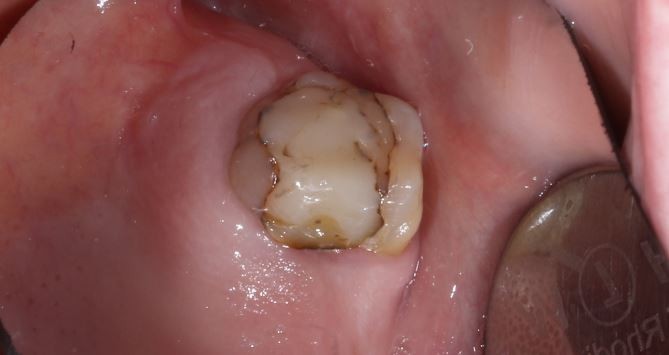

Тумашевич Ольга Олеговна: портфолио (1)